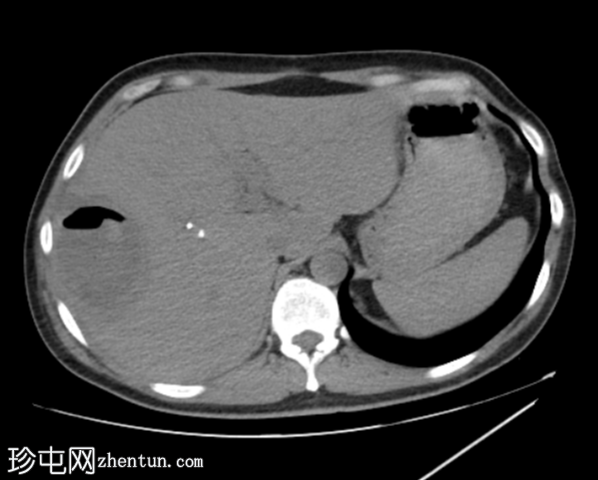

2.png

平扫

平扫图像显示胆囊切除夹、胆道积气、胆总管支架及右肝叶VIII段囊性病变伴气液平面。

增强扫描图像显示囊肿边缘强化,周围可见晕环,呈双靶征。